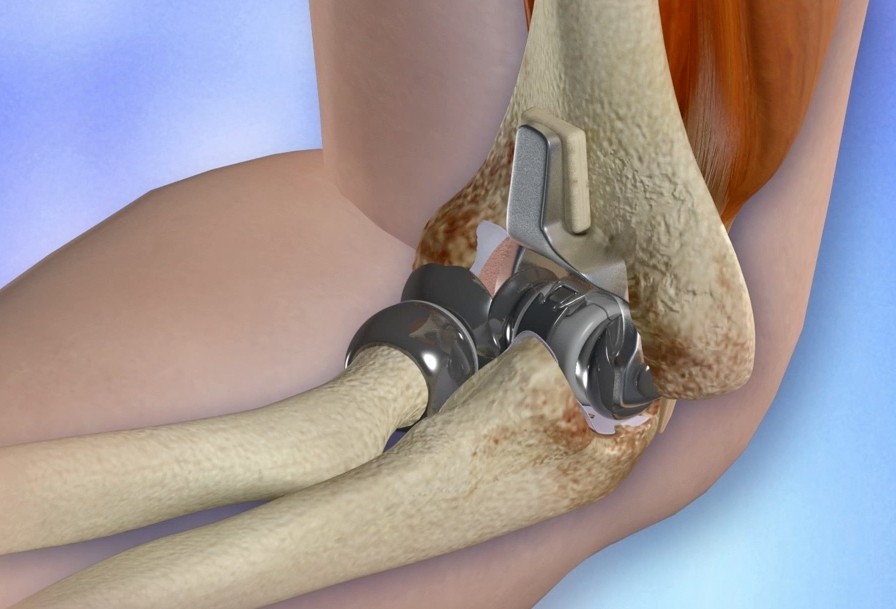

其实还有很多种疾病可能导致肘关节出现类似的问题,比如肘关节的结核,肘关节的骨肿瘤,或者是一种非常少见的疾病,肘关节的夏科氏关节,这种问题会让患者在潜移默化当中慢慢的出现整个骨关节的改变,但是患者却没有任何的症状,而一旦患者出现了问题,就将是非常难处理的这种状况,整个骨关节将变得乱马七糟,只有通过关节置换才能帮助患者解决一定的问题。